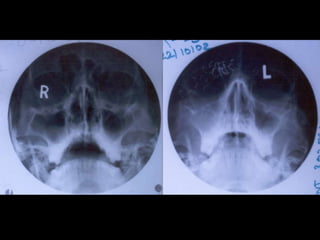

• X-ray PNS

• CT Scan PNS (Coronal and Axial views)

• Haematological TC, DC,Hb%, ESR Absolute eosinophil count • X-ray PNS • CT Scan PNS (Coronal and Axial views) DNE INVESTIGATIONS